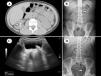

Se realizaron 5.909 litotricias, de las cuales el 1% correspondían a una población menor de 18 años (n=59): edad mediana 7 años (rango: 1-17), 50% mujeres (n=30). El tamaño de la litiasis fue de 1cm (rango: 0,8-4). El 78% de los pacientes tenía un solo cálculo (n=46), el 10% tenía 2 (n=6) y el 12% tenía 3 o más litiasis (n=7). El 61% de los cálculos estaban en riñón (n=36), 20/59 en uréter (33%), 2 en vejiga y un paciente presentaba nefro-ureterolitiasis (fig. 2). La duración media del tratamiento fue de 45±18min, el número medio de ondas de 2.135 con una potencia máxima de 8±3kV y un tiempo de fluoroscopia de 4,2±3min. La dosis de radiación fue de 11±10,5Gy/cm2. Tan solo 11/59 pacientes tenían estudio de la litiasis, siendo lo más frecuente los cálculos de oxalato cálcico-fosfato cálcico (3/11) y oxalato cálcico (3/11), seguidos de las litiasis por fosfato cálcico (2/11), apatita-fosfato cálcico (2/11) y cistina (1/11). Quince pacientes precisaron retratamiento (25%): 9/15 necesitaron un retratamiento (60%), 4/15 precisaron 2 sesiones y 2/15 requirieron 4 sesiones (13%) debido a recidiva temprana. La tasa de complicaciones tras la LEOC fue del 10% (n=6/59), en 4 casos se trataba de dolor abdominal que precisaron ingreso para tratamiento analgésico solo en un enfermo, y los otros 2 eventos fueron episodios febriles con leucocituria, pero urocultivo negativo. Ningún paciente presentó calle litiásica post-LEOC. Al tratarse de un centro de referencia, muchos pacientes eran controlados en otras instituciones, por lo que hemos perdido del seguimiento a 21/59 niños (35,5%). En los 38 casos que hemos logrado seguir, la tasa de éxito (ausencia de litiasis o residuo <3mm) fue del 84% (n=32) a los 12 meses del tratamiento. En estos pacientes se realizó un análisis estratificado de la tasa de éxito por grupos etarios: 0-6 años (n=15): 93%; 6,1-12 años (n=11): 72%; y 12,1-18 años (n=12): 83%, sin encontrar diferencias significativas (p=0,109). Tampoco se documentaron diferencias estadísticas entre los grupos etarios según el tamaño o localización de la litiasis (p=0,083 y 0,231, respectivamente); aunque en los niños de 0-6 años con nefrolitiasis la LEOC mostró mayor efectividad (100%) que en los pacientes de 6-12 (57%) y 12-18 años (80%).